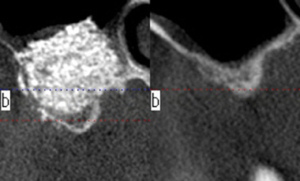

歯周病で歯ぐきに出血・炎症・膿があると、化学物質が血管を経由して血糖値を下げるインシュリンの働きを阻害します。

その結果、糖尿病になります。

炎症のある歯周ポケットの表面積は、手のひらサイズにもなります。手のひらサイズの出血・膿が治療なしで

そのまま放置されている。と考えると、ゾッとしませんか?

糖尿病は血管をボロボロにします。歯周病菌も血管をボロボロにします。